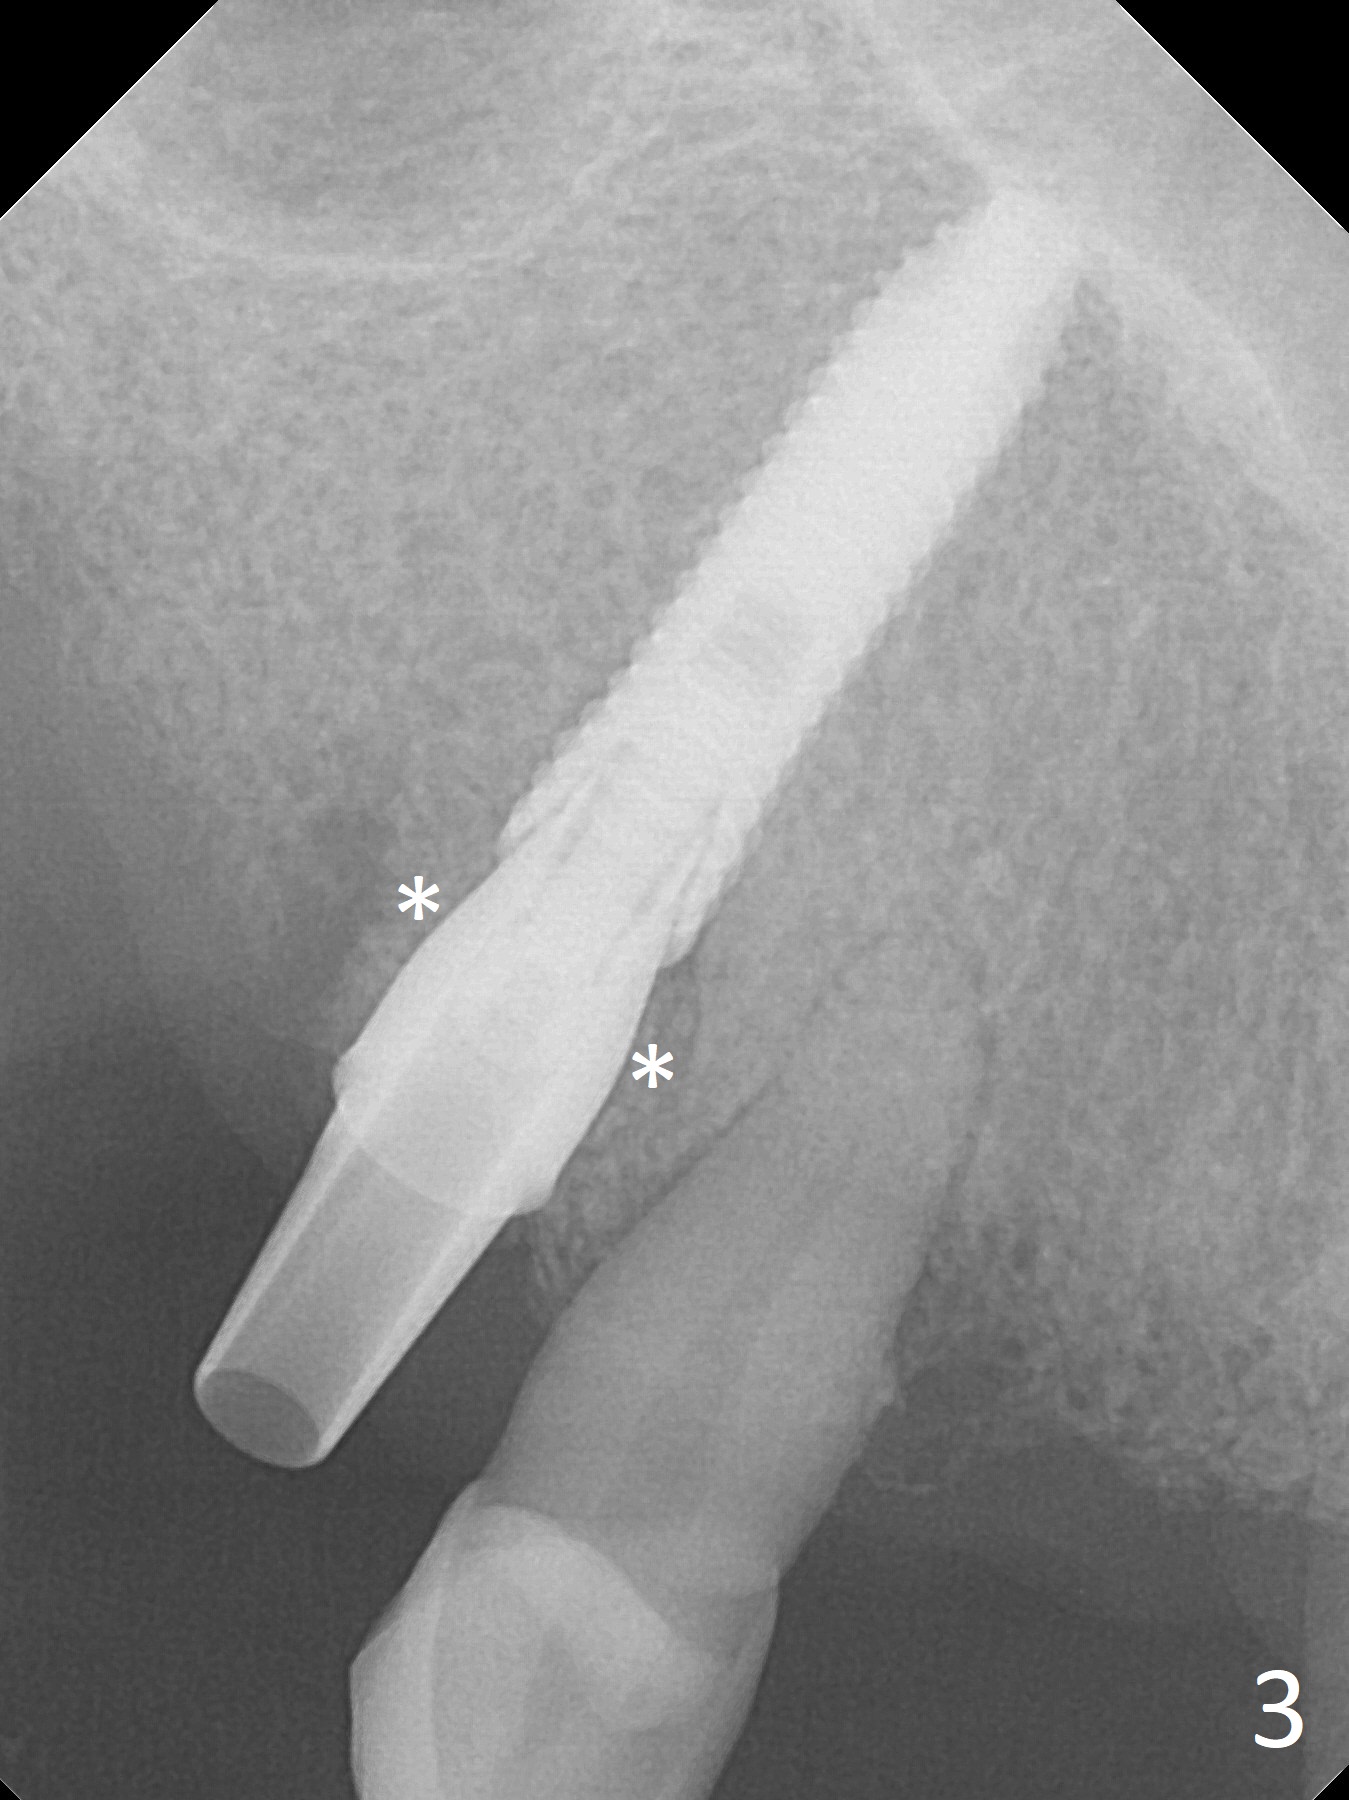

Extraction of the tooth #5 with mobility III reveals no buccal plate and low palatal plate. Osteotomy starts as palatal as possible (Fig.1). The bone density is low. After use of 2.7 mm drill (Fig.2), a 3 mm drill can be inserted into the osteotomy without resistance. A 4x16 mm implant is placed with insertion torque <30 Ncm. When an abutment is placed, the implant is found to have been placed distal. The implant is untorqued for change in trajectory. When a 4.5x7(5) mm abutment is placed, the abutment turns with the underlying implant (Fig.3). The former is kept to be turned with a hand driver until the latter is unable to turn. Following placement of allograft (Fi.g3,4 *), a mini-provisional is fabricated to retain the bone graft and at the same time not to be interfered with when a flipper is in and out. The bone graft in the former socket gap appears to have integrated into the native one 4.5 months postop (Fig.5).